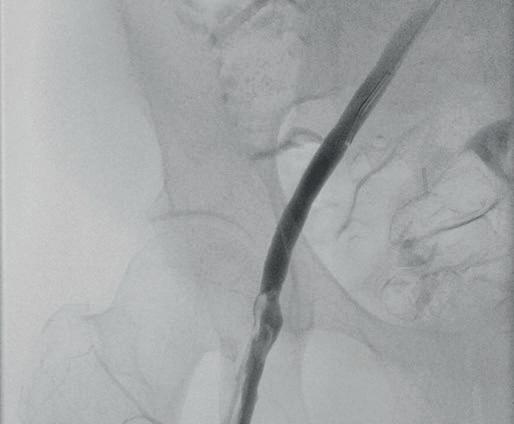

Left: Pre- and postoperative images (courtesy of Dittmar Böckler) of the first European implantation of the Gore Tag TBE; above: Dittmar Böckler performing the implantation